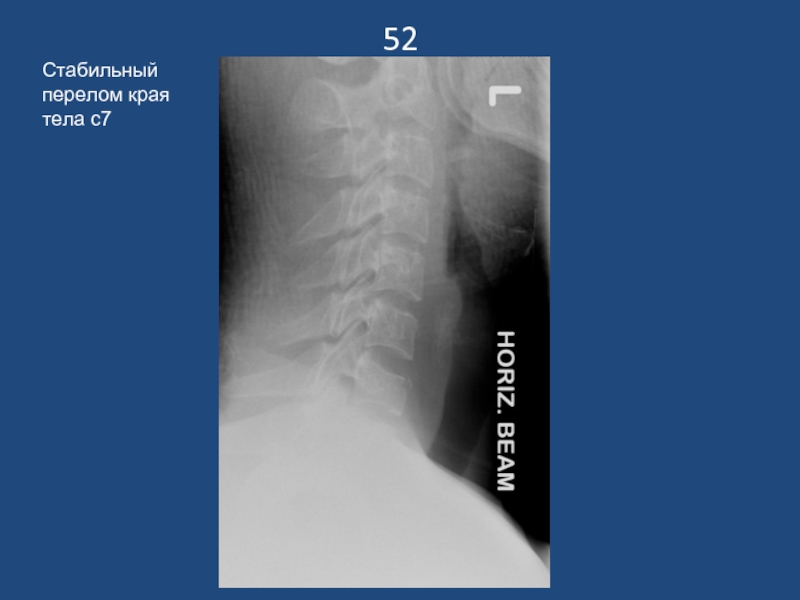

Слайд 5352

Стабильный перелом края тела с7